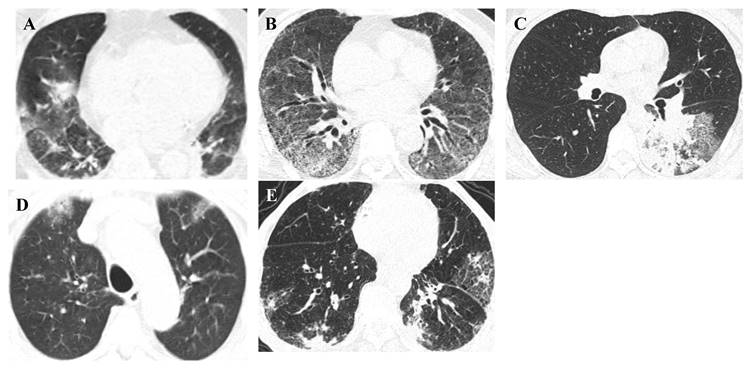

Radiological diagnosis

Radiological diagnosis is essential for the evaluation of suspected or confirmed infectious patients with an initial diagnosis, evaluation of disease progression and complications, and monitoring the response for appropriate disease management [84]. Different respiratory infections cause abnormal symptoms in the lung parenchyma (internal structures, texture, and density) that can be seen on conventional imaging modalities, such as chest computed tomography (CT). Furthermore, developing a deep learning algorithm, Pneumonia-Plus, based on CT images may be utilised to screen and differentiate between bacterial, fungal, and viral pneumonia, which reduces the risk of misdiagnosis and is important for appropriate treatment, avoiding the use of unnecessary antibiotics and providing timely information to guide clinical decision-making and improve patient outcomes [85,86]. Representative high-resolution CT (HRCT) scan images of pulmonary lesions with respiratory pathogenic microbes are shown in Figure 4.

Figure 4

Representative HRCT-scan images of pulmonary lesions. Representative (A) adenovirus pneumonia, HRCT: Both lungs show patchy consolidation with ground-glass opacities, (B) respiratory syncytial virus pneumonia, HRCT: Both lungs show ground-glass opacities and reticular high-density shadows, (C) Mycoplasma pneumoniae pneumonia, HRCT: The lower lobe of the left lung shows patchy high-density shadows and reticular high-density shadows, (D) COVID-19 pneumonia, HRCT: Both lungs show subpleural patchy ground-glass opacities, (E) influenza virus A pneumonia, HRCT: Both lungs show patchy high-density shadows and reticular high-density shadows under the pleura.